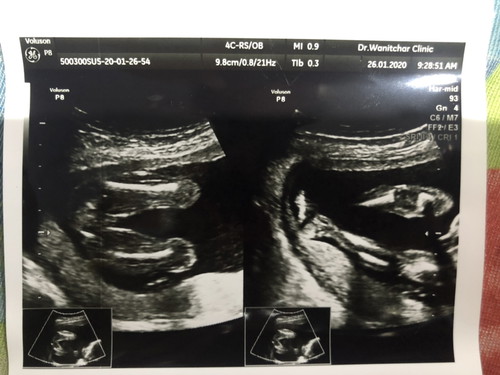

ญ หรือ ช

ขอความเห็นจากแม่ๆหน่อยจ้า

ชายค่ะ เห็นกระจู๋